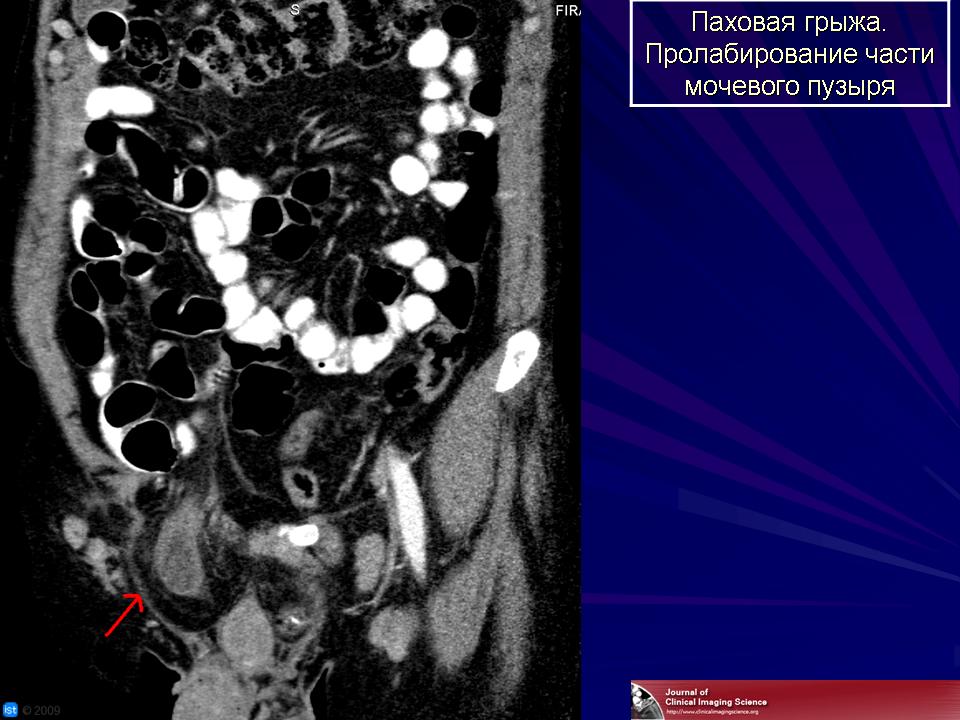

Заболевания мочевого пузыря. Tue, 31/05/2011 - 23:36 #1 Катенёв Валенти... Offline Last seen: 7 years 4 months ago Joined: 22.03.2008 - 22:15 Posts: 54876 Малокоплакия.Приложения: Fri, 03/06/2011 - 23:06 #2 Катенёв Валенти... Offline Last seen: 7 years 4 months ago Joined: 22.03.2008 - 22:15 Posts: 54876 Эмфизематозный циститПриложения: Tue, 05/07/2011 - 01:45 #3 Катенёв Валенти... Offline Last seen: 7 years 4 months ago Joined: 22.03.2008 - 22:15 Posts: 54876 Продолжение. Приложения: Sun, 03/06/2012 - 01:38 #4 Катенёв Валенти... Offline Last seen: 7 years 4 months ago Joined: 22.03.2008 - 22:15 Posts: 54876 Дивертикулы мочевого пузыря. Приложения: Sat, 23/03/2013 - 21:24 #5 Катенёв Валенти... Offline Last seen: 7 years 4 months ago Joined: 22.03.2008 - 22:15 Posts: 54876 Нейрогенный мочевой пузырь http://radiopaedia.org/cases/christmas-tree-bladder http://radiopaedia.org/articles/neurogenic_bladder http://radiology.rsna.org/content/76/5/795Приложения: Wed, 03/04/2013 - 17:24 #6 Катенёв Валенти... Offline Last seen: 7 years 4 months ago Joined: 22.03.2008 - 22:15 Posts: 54876 Эмфизематозный цистит http://www.wikiradiography.com/page/Emphysematous+Cystitis Fri, 30/08/2013 - 21:51 #7 Катенёв Валенти... Offline Last seen: 7 years 4 months ago Joined: 22.03.2008 - 22:15 Posts: 54876 Эмфизематозный цистит ID: 17035 Emphysematous cystitis Dr Andrew Dixon - 11 Mar 2012 Rim of gas lucency outlining the wall of the bladder consistent with emp... ID: 18853 Emphysematous cystitis Dr Maxime St-Amant - 25 Jul 2012 Related article:Emphysematous cystitis ID: 16738 Emphysematous cystitis Dr Chris O'Donnell - 16 Feb 2012 Related articlesEmphysematous cystitis ID: 7551 Emphysematous cystitis Dr Frank Gaillard - 8 Nov 2009 Emphysematous cystitis in a 70 year old diabetic woman. Incidental findi... ID: 23558 Emphysematous cystitis Dr Augusto César Vieira Teixeira - 23 Jun 2013 Emphysematous cystitis represents a rare form of acute inflammation of t... Случаи и цифры Корпус: прозрачная пленка Случай 1: ультразвук Случай 2 Случай 3 Случай 4 Случай 5 Случай 6 Случай 7 Случай 8 Thu, 27/03/2014 - 10:31 #8 Катенёв Валенти... Offline Last seen: 7 years 4 months ago Joined: 22.03.2008 - 22:15 Posts: 54876 Лимфогранулематоз Приложения: Sat, 10/03/2018 - 14:14 #9 Катенёв Валенти... Offline Last seen: 7 years 4 months ago Joined: 22.03.2008 - 22:15 Posts: 54876 Эмфизематозный цистит. http://www.nejm.org/doi/full/10.1056/NEJMicm1509543 Приложения: Sat, 10/03/2018 - 17:27 #10 Катенёв Валенти... Offline Last seen: 7 years 4 months ago Joined: 22.03.2008 - 22:15 Posts: 54876 Кальцификации мочевого пузыря. http://www.nejm.org/doi/full/10.1056/NEJMicm1504759 Приложения: